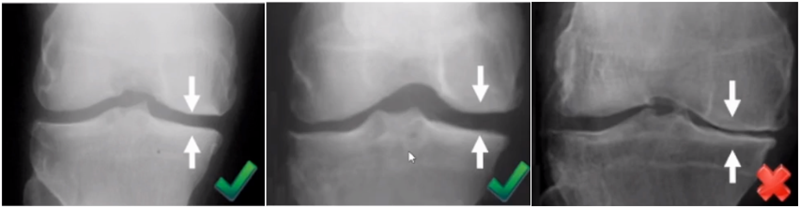

二、单髁置换的适应证——外翻应力片

屈曲20°外翻应力:看外侧软骨

外翻应力片可以辅助评价外侧间室关节软骨厚度是否正常,以及内侧副韧带功能是否完整。外侧全层软骨、外侧有骨赘的情况下都不是禁忌证,如外侧出现软骨磨损则为禁忌证。

外翻应力片还可以观察内侧间隙,如内侧副韧带出现挛缩,间隙狭窄,那么此时不适合单髁。

检查时注意X线的投照角度要平行于关节线方向,以保证准确。

可以矫正畸形,恢复关节间隙和MCL张力